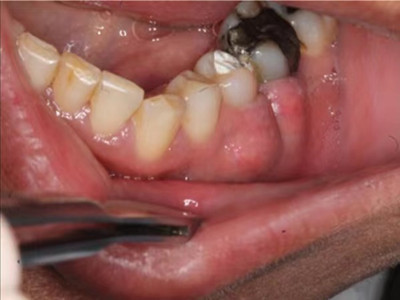

根尖囊肿需有专业医生通过取上颌窦根治术式切除囊肿。若病牙尚稳固,有保留可能,则行根尖切除或根管治疗以避免囊肿再发。否则,应同时拔除病牙。